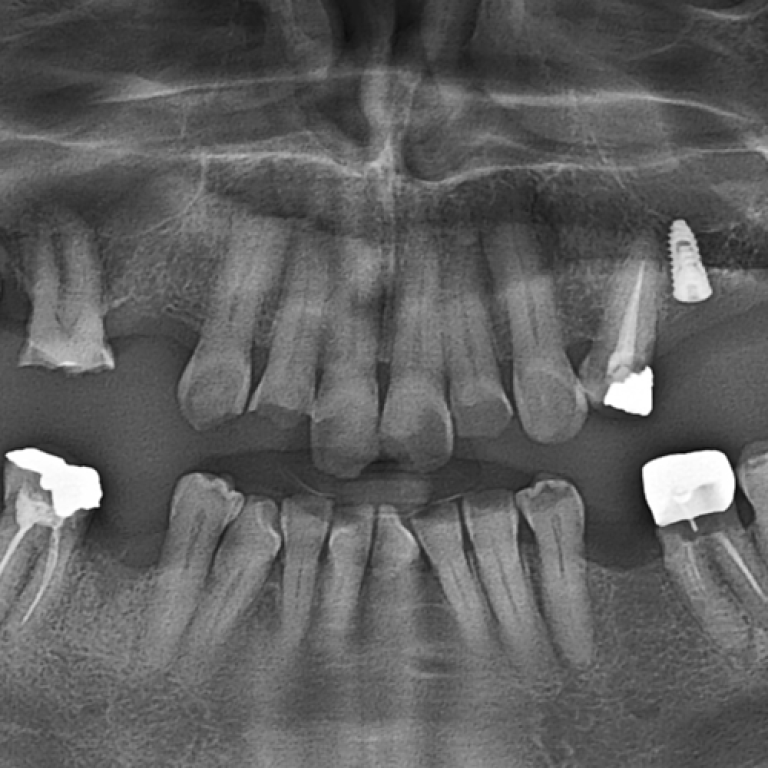

Renew and revitalize your smile with our restorative dentistry services, including crowns, bridges, and fillings, ensuring a seamless …